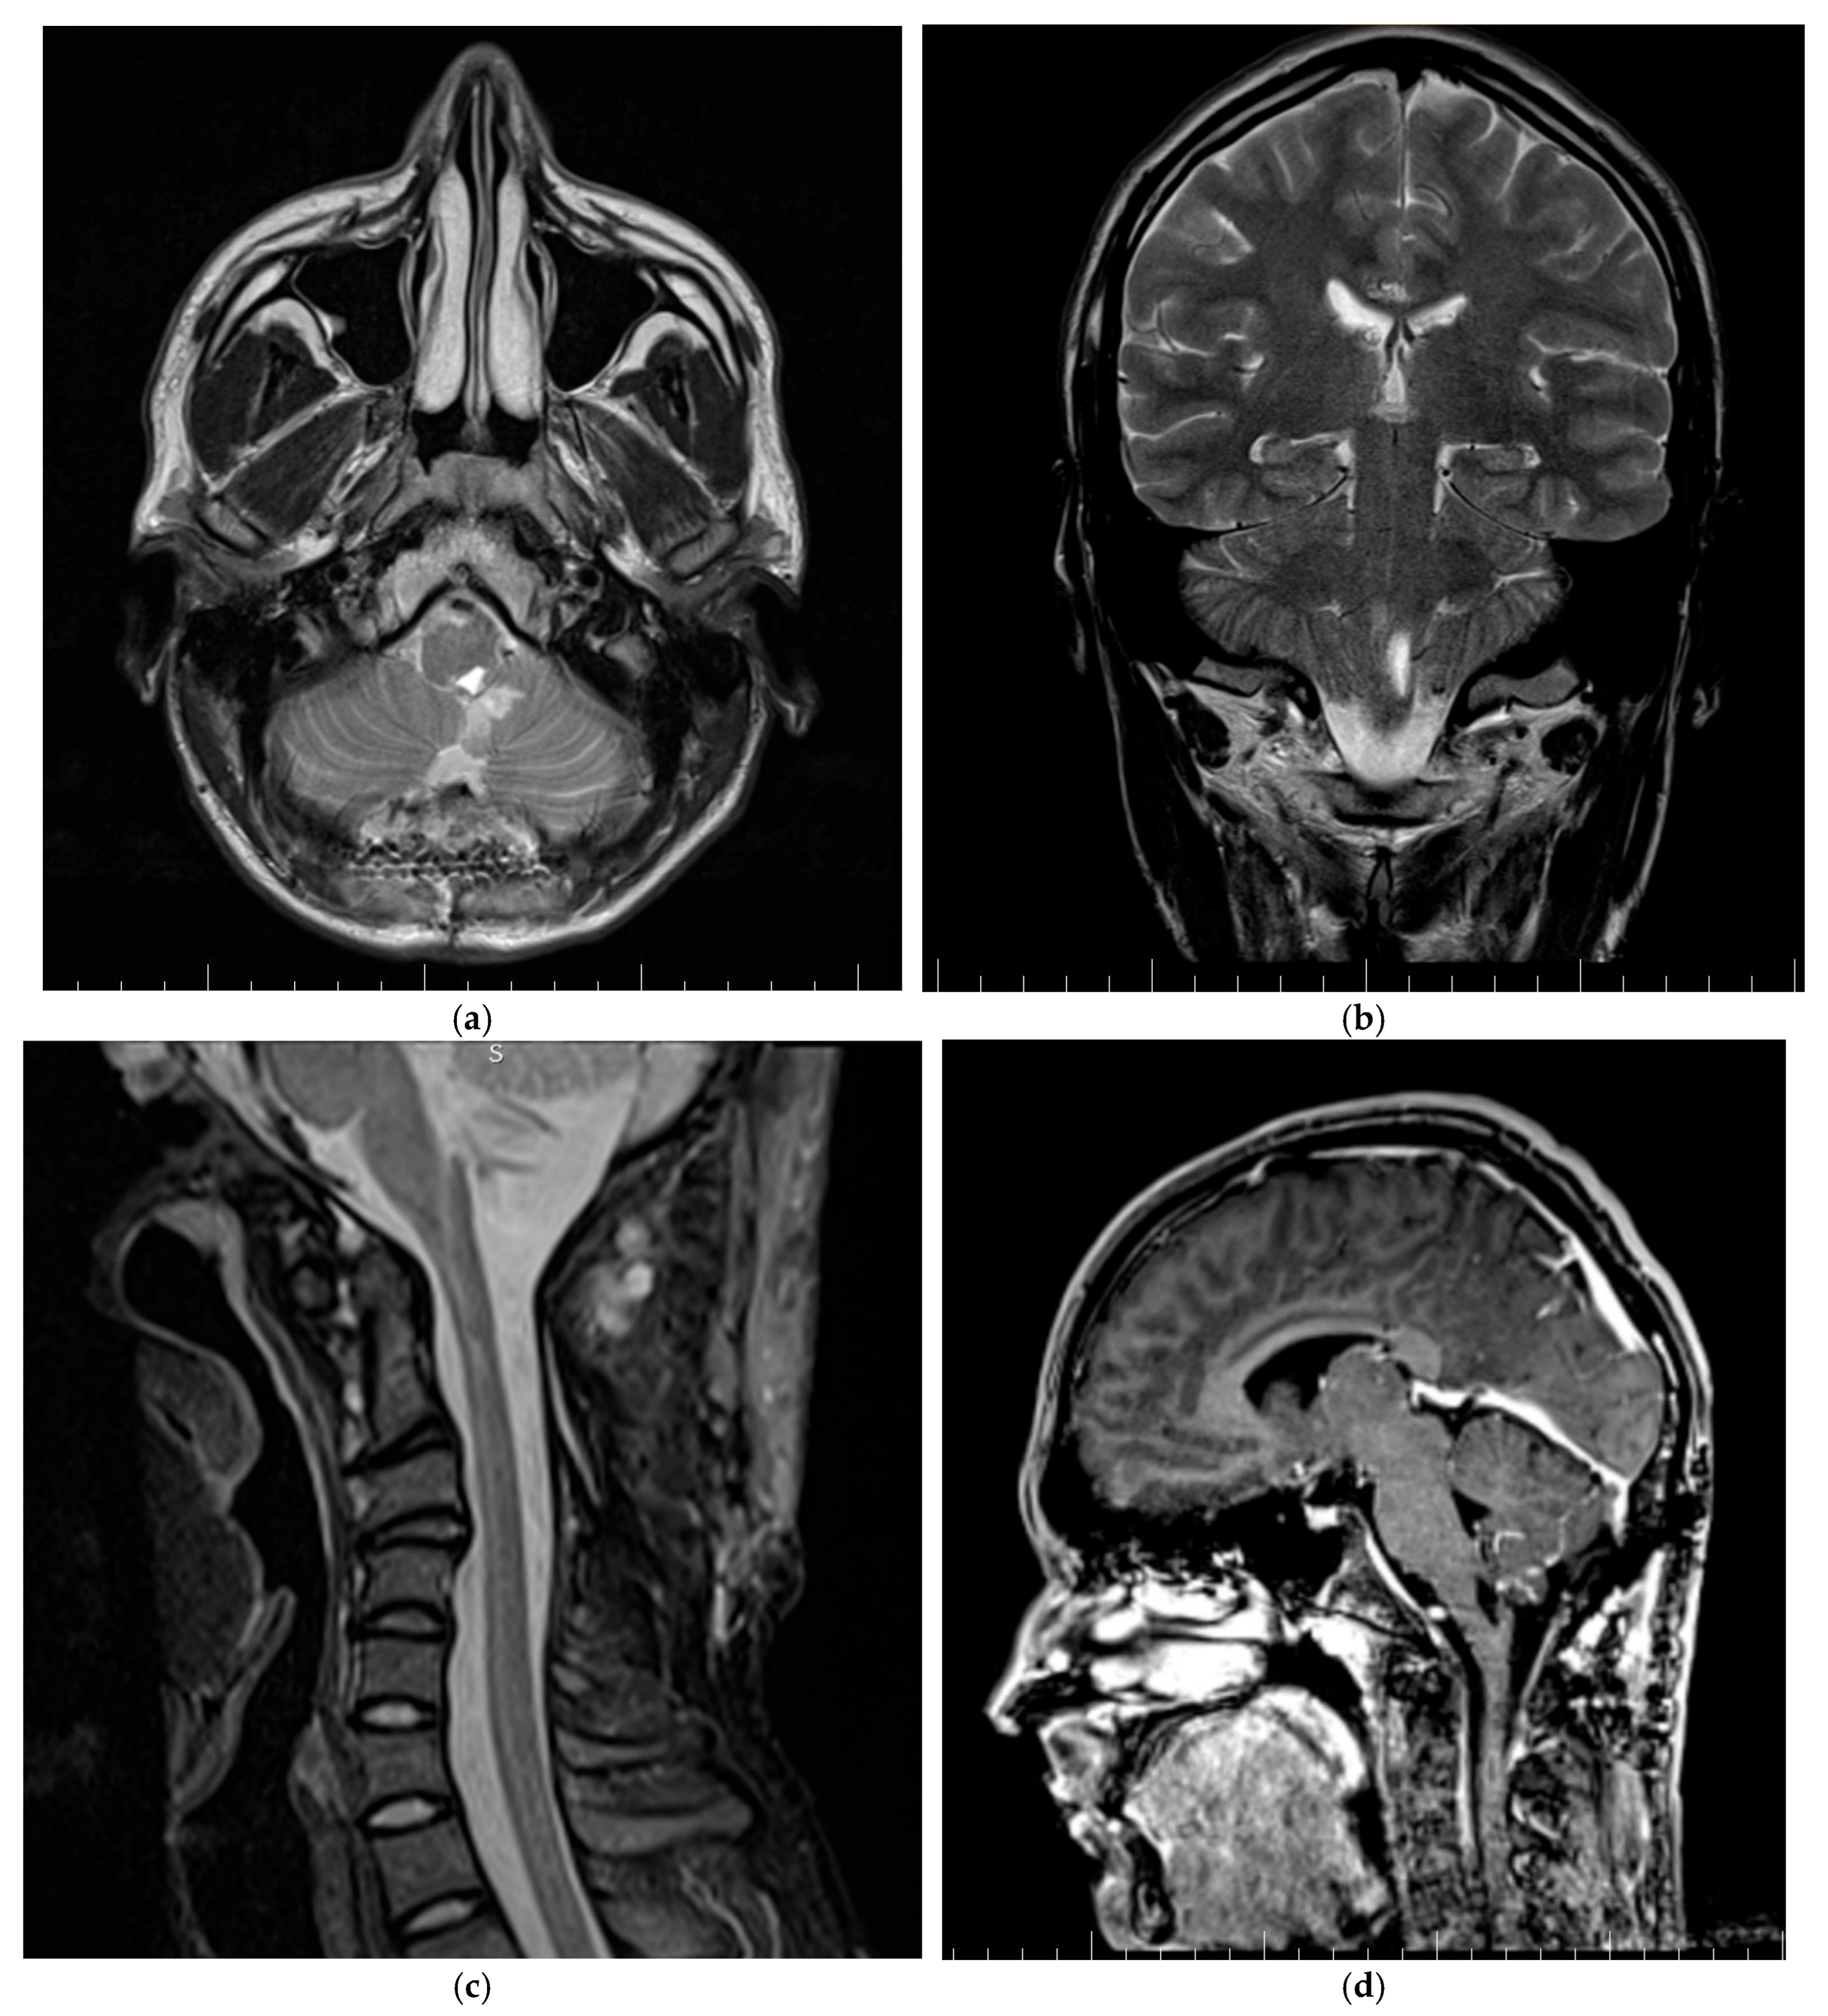

3.1.1. Patient One

3.1.2. Patient Two

3.1.3. Patient Three